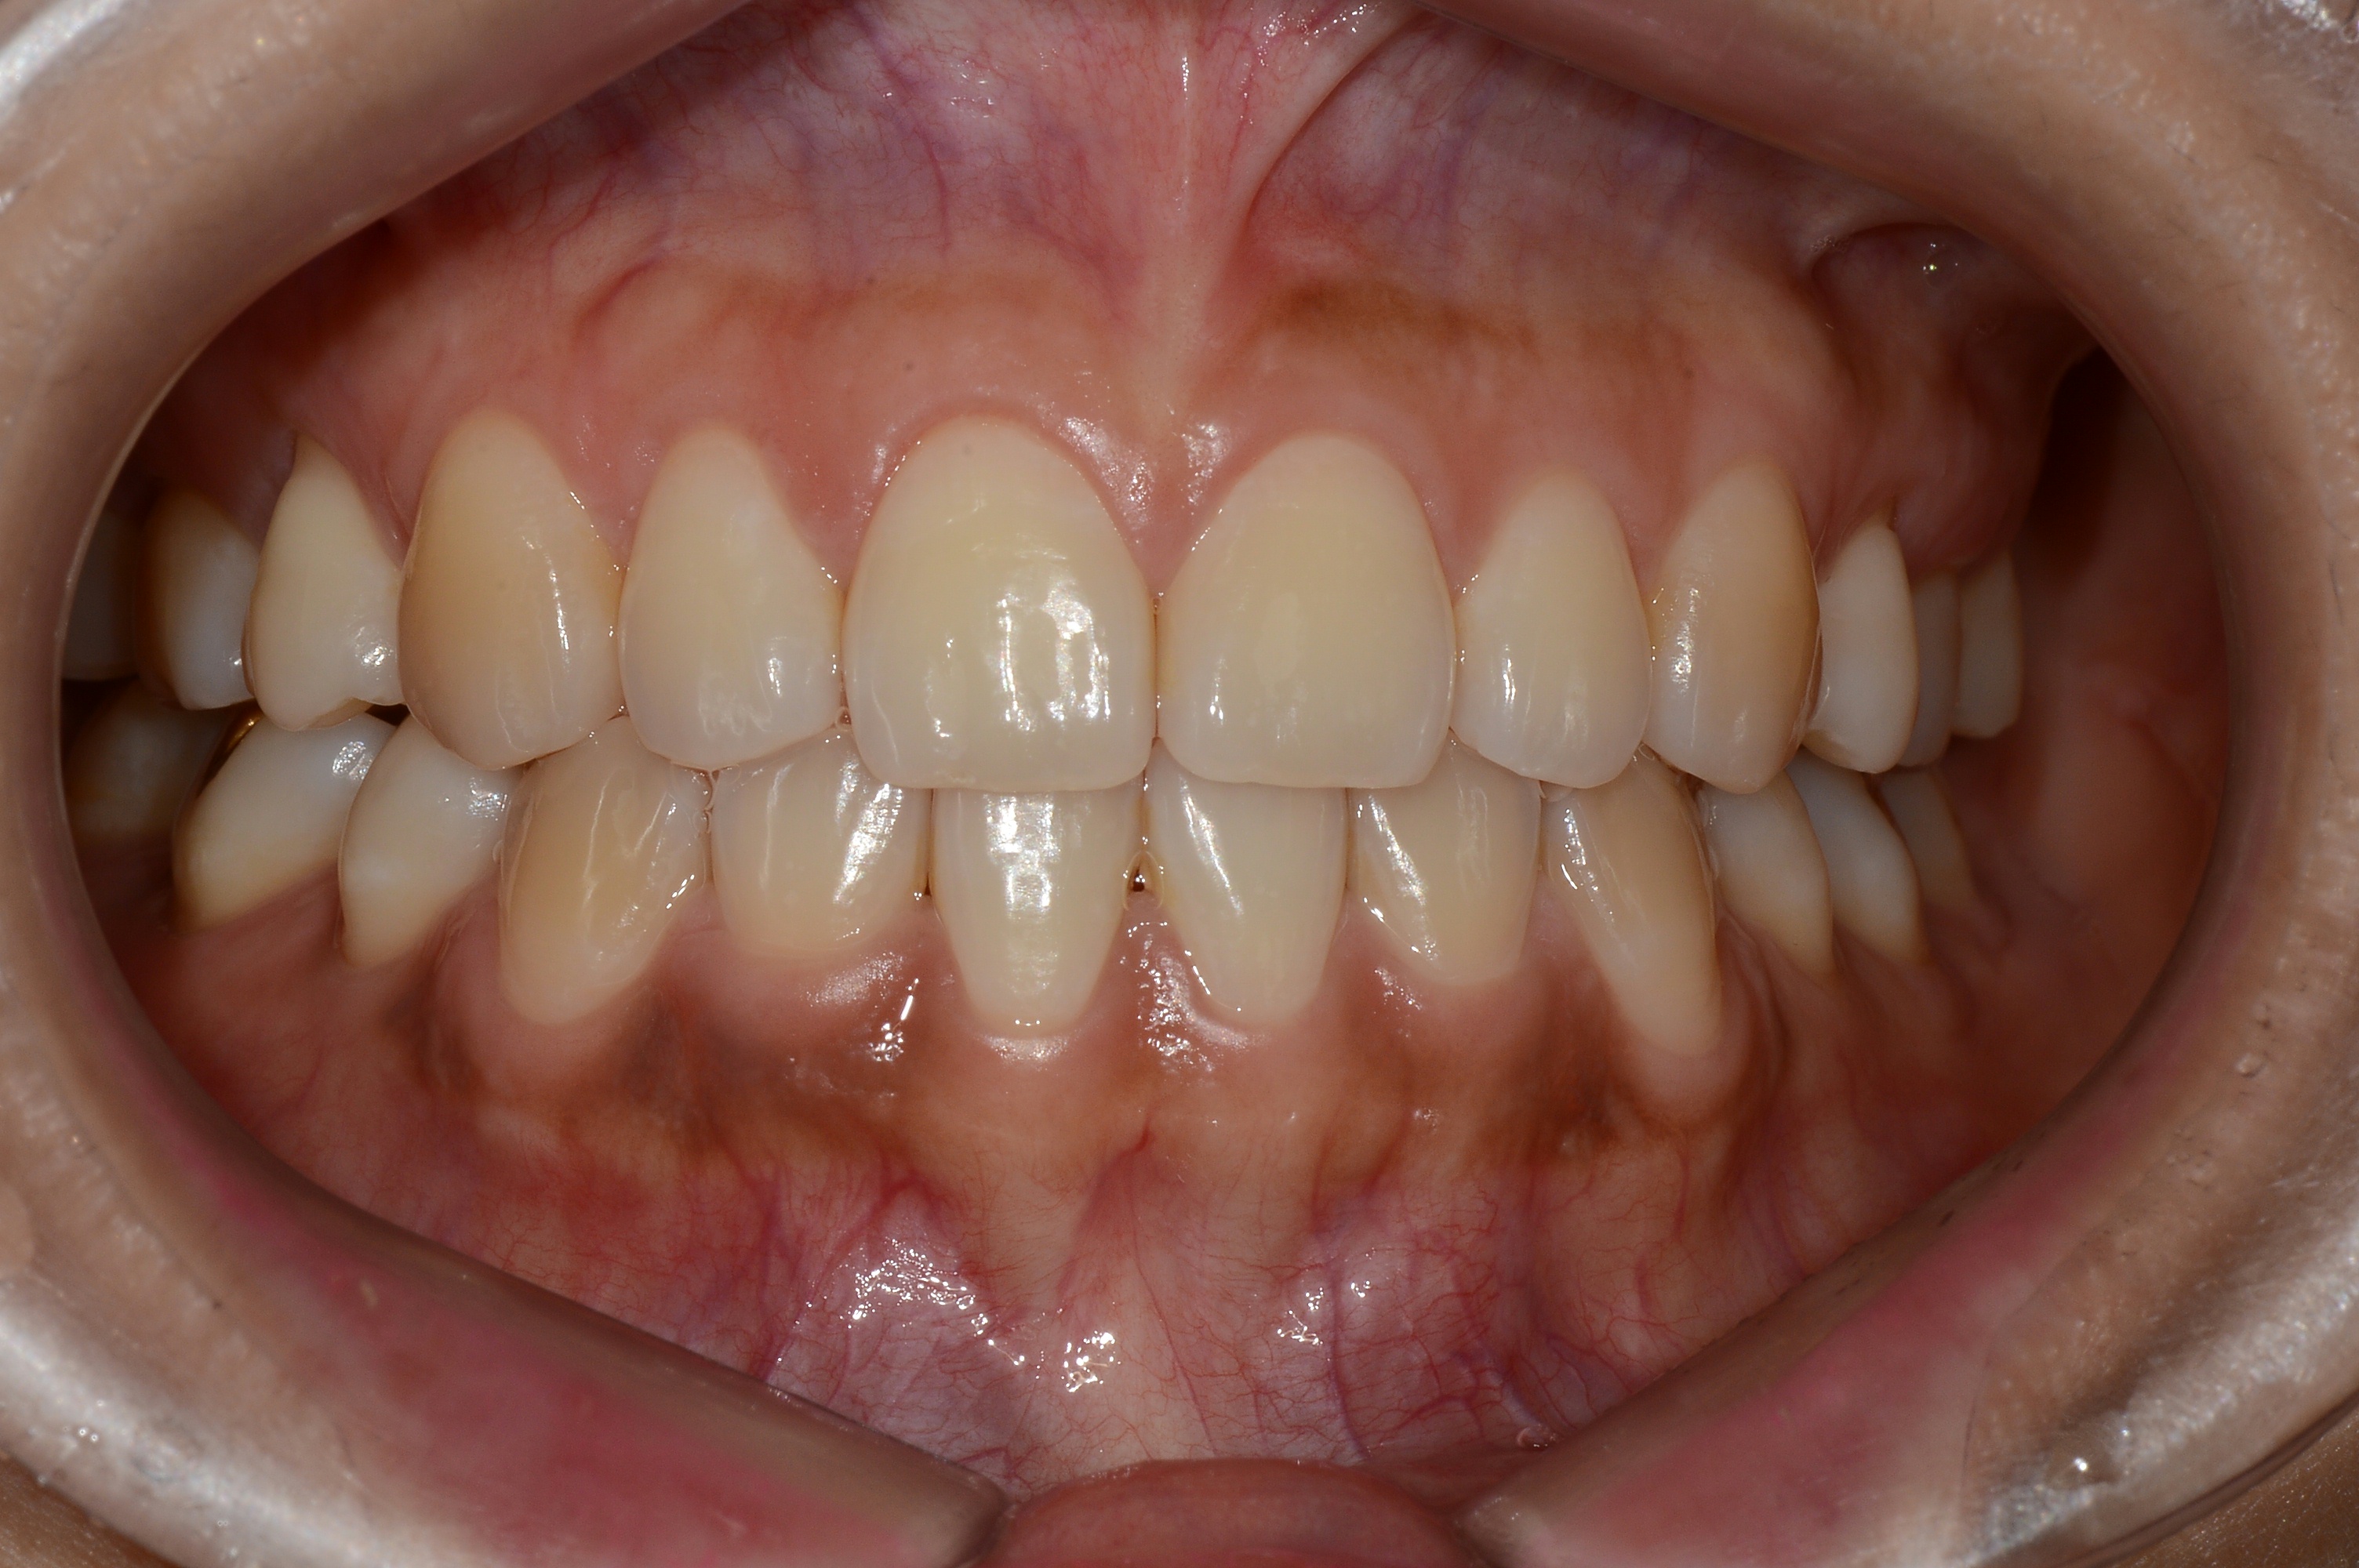

치료 후 사진입니다.